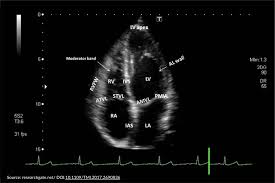

Echocardiogram

An ultrasound of the heart that shows how the chambers and valves move and pump. It’s non-invasive and provides crucial insights into your heart’s structure and function.